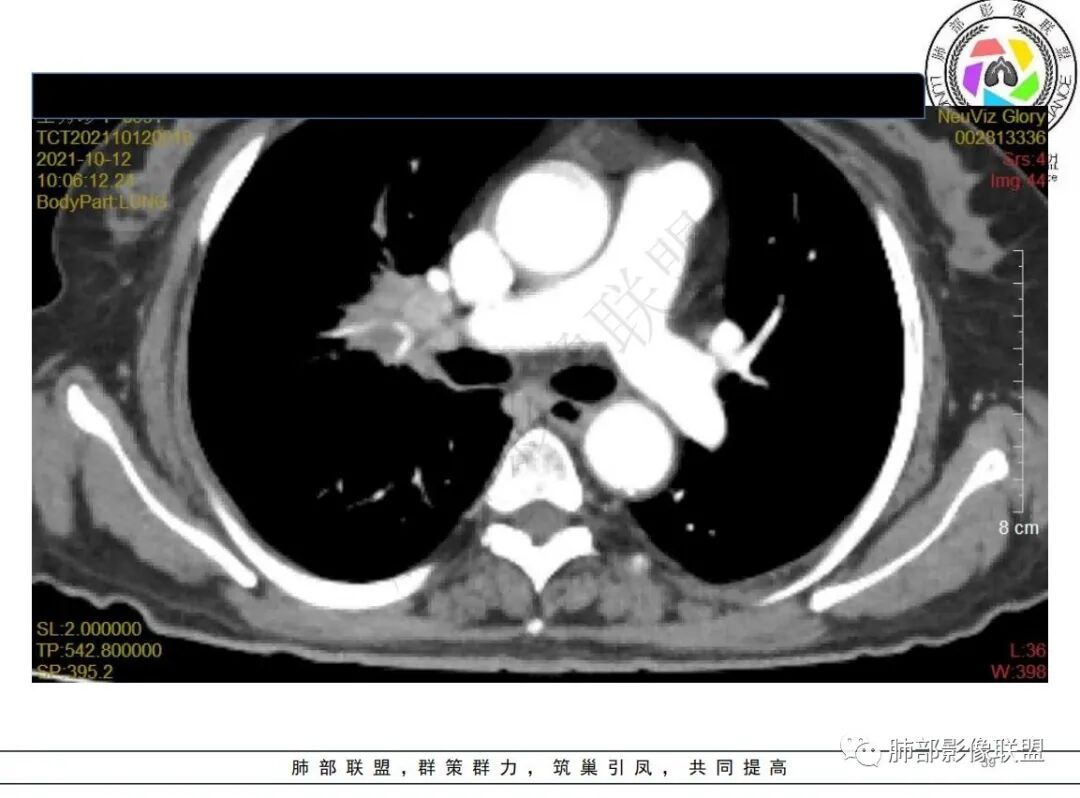

白血病化疗后,出现多发结节,边缘可见晕征,病灶内可见多发坏死,右肺中叶肺动脉可见充盈缺损,右肺中叶可见融冰征,考虑毛霉菌,右肺中叶肺动脉栓塞伴右肺中叶肺梗死。

有白血病病史,免疫妥协,双肺多发结节,纵隔增大淋巴结,短期抗炎治疗后复查,病灶明显增大,右肺门肿块,内可见坏死,临近肺动脉受侵,支气管闭塞,周围见阻塞性炎症,考虑感染性病变,毛霉菌可能大

4.白血病化疗后,CT上出现多发结节,边缘可见晕征,病灶内可见多发坏死,右肺中叶肺动脉可见充盈缺损,右肺中叶可见融冰征,右肺中叶肺动脉侵犯栓塞伴右肺中叶肺梗死,可符合真菌感染。

血管侵袭性曲霉病是最常见的类型,其特征是真菌菌丝侵入和阻塞中小肺动脉,形成凝固性坏死、肺泡出血或出血性梗死。

6.肺曲霉病典型的CT表现是结节周围有磨玻璃样的晕征表现,或胸膜为宽基底的楔形实变。晕征表现为曲菌感染的肺结节伴梗死和凝固性坏死,周围有肺泡出血。最终可出现空泡征象,并可观察到中央坏死组织与周围肺实质分离形成空气新月征。